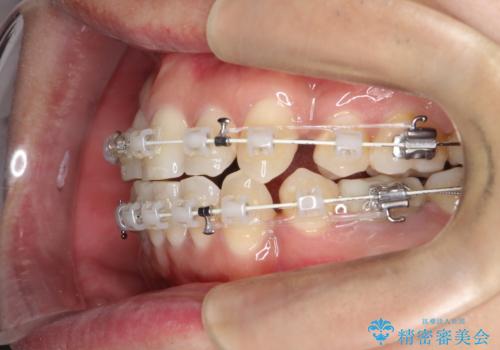

重度の叢生を抜歯矯正で改善|審美ワイヤー矯正+海外出張に伴う中断・再開対応

- 治療計画: 重度の叢生を改善するため、上下左右の小臼歯抜歯を伴う審美ワイヤー矯正を計画しました。抜歯により得られたスペースを利用して歯を整列させ、適切な噛み合わせを目指します。途中、患者様が1年間の海外出張となったため、一時的にワイヤーを外し、保定装置で現状維持を図りました。帰国後に再度審美ワイヤー矯正を再開し、仕上げ調整を行い治療完了を目指します。

重度の叢生により、抜歯を伴う矯正が必要と判断しました。目立ちにくい透明な審美ブラケットを用いたワイヤー矯正を実施しましたが、治療途中での海外出張が決定したため、一度矯正装置を取り外し、保定装置で現状維持を行いました。帰国後に改めて装置を装着し矯正を再開。患者様のライフスタイルに柔軟に対応しながら、最終的には理想的な歯並びと美しい口元を実現しました。